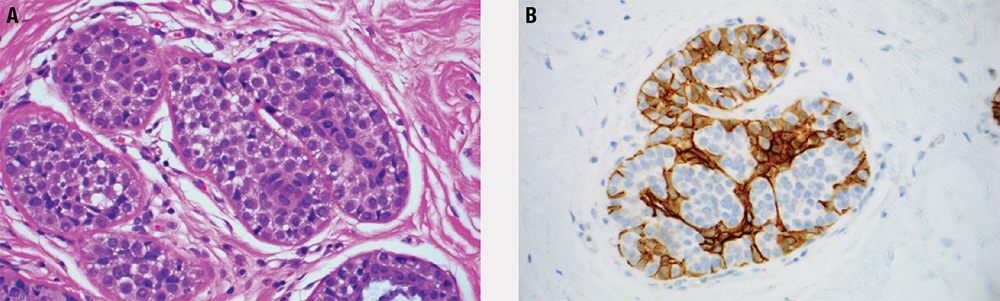

Prototypical morphology

- UDH is identified when the ductal epithelium exceeds the normal one- to two-cell thickness, after accounting for tangential sectioning and other artifacts.

- Mild UDH is present when the ductal epithelium is up to four cells thick; on the other end of the spectrum, florid UDH fills duct lumens, while moderate UDH is between these extremes.

- The essential features of UDH, in contrast to DCIS and ADH, include cellular heterogeneity and architectural disorganization.

- The hyperplastic cellular population is cytologically heterogeneous and haphazardly arranged, with irregular cell spacing; the effect of this unevenness is luminal structures with rough, wavy borders and elongated, slit-like spaces (Figure 5-7).

- These slit-like spaces are typically found at the periphery of the duct lumen, with intervening epithelial “bridges” that are tapered rather than stout.

- Micropapillary UDH usually has broad-based elongated micropapillae with tapering ends (unlike ADH, which has narrow-based, short, bulbous micropapillae).

- The epithelium may appear spindled and “streaming,” particularly in “bridges” between adjacent spaces where the cells are generally aligned parallel to the lumen and may lay flat against it.

- Individual ductal epithelial cell nuclei are oval and frequently grooved. They have pale dispersed chromatin and small indistinct nucleoli.

Special studies

- CK5 (or other basal keratins) and CK8/18 (luminal keratins) show a mosaic pattern of expression—a reflection of cellular heterogeneity—in contrast to low-grade DCIS and ADH, which are uniformly negative.

- Similarly, ER shows patchy and variable positivity in UDH, in contrast to strong and diffuse expression in ADH and low-grade DCIS.